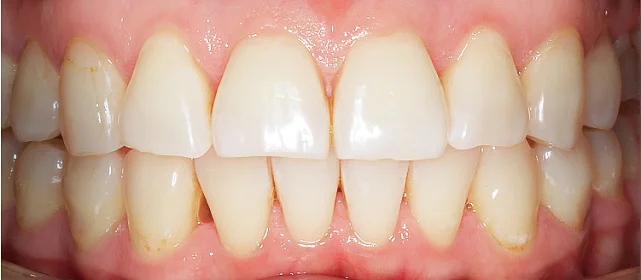

Зубы выровнены, смыкание нормализовано. Установлены несъёмные ретейнеры на обе челюсти, изготовлены ретенционные капы. Пациентка предварительно проконсультирована ортопедом онлайн.

Решение: Поставили элайнеры 3D Smile на обе челюсти. Лечение заняло 4 года и потребовало нескольких последовательных этапов коррекции. Капы менялись каждые 1–2 недели, на контрольных визитах отслеживали прогресс и выдавали новые наборы. Зубы встали в правильное положение, смыкание нормализовалось. Зафиксировали ретейнеры на обе челюсти, изготовили ретенционные капы. Пациентка прошла онлайн-консультацию с ортопедом для оценки дальнейших шагов.